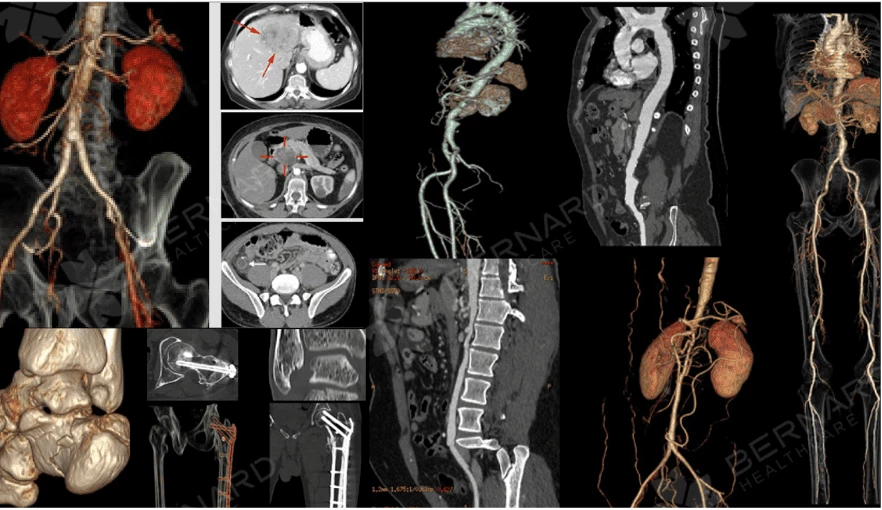

Thông qua hệ thống PACS kết nối trực tiếp, hình ảnh CT Scan của bệnh nhân được gửi sang Nhật Bản. Chỉ sau thời gian ngắn, giáo sư - bác sĩ chẩn đoán hình ảnh Bệnh viện Đại học Yamanashi đã phản hồi báo cáo chi tiết.

Đánh giá từ chuyên gia Nhật Bản đồng ý rằng đây là ung thư amidan phải và di căn nhiều hạch cổ phải. Bệnh nhân được khuyến cáo thực hiện MRI vùng cổ để đánh giá rõ ràng hơn mức độ xâm lấn mô mềm và chụp FDG-PET để đánh giá phạm vi di căn.

Nhờ độ phân giải cao và khả năng dựng hình 3D, CT Scan giúp bác sĩ nhìn rõ cấu trúc khối u và hệ mạch nuôi u, từ đó có thể đánh giá giai đoạn bệnh (staging), lên kế hoạch điều trị phù hợp và theo dõi đáp ứng điều trị trong những lần kiểm tra tiếp theo.